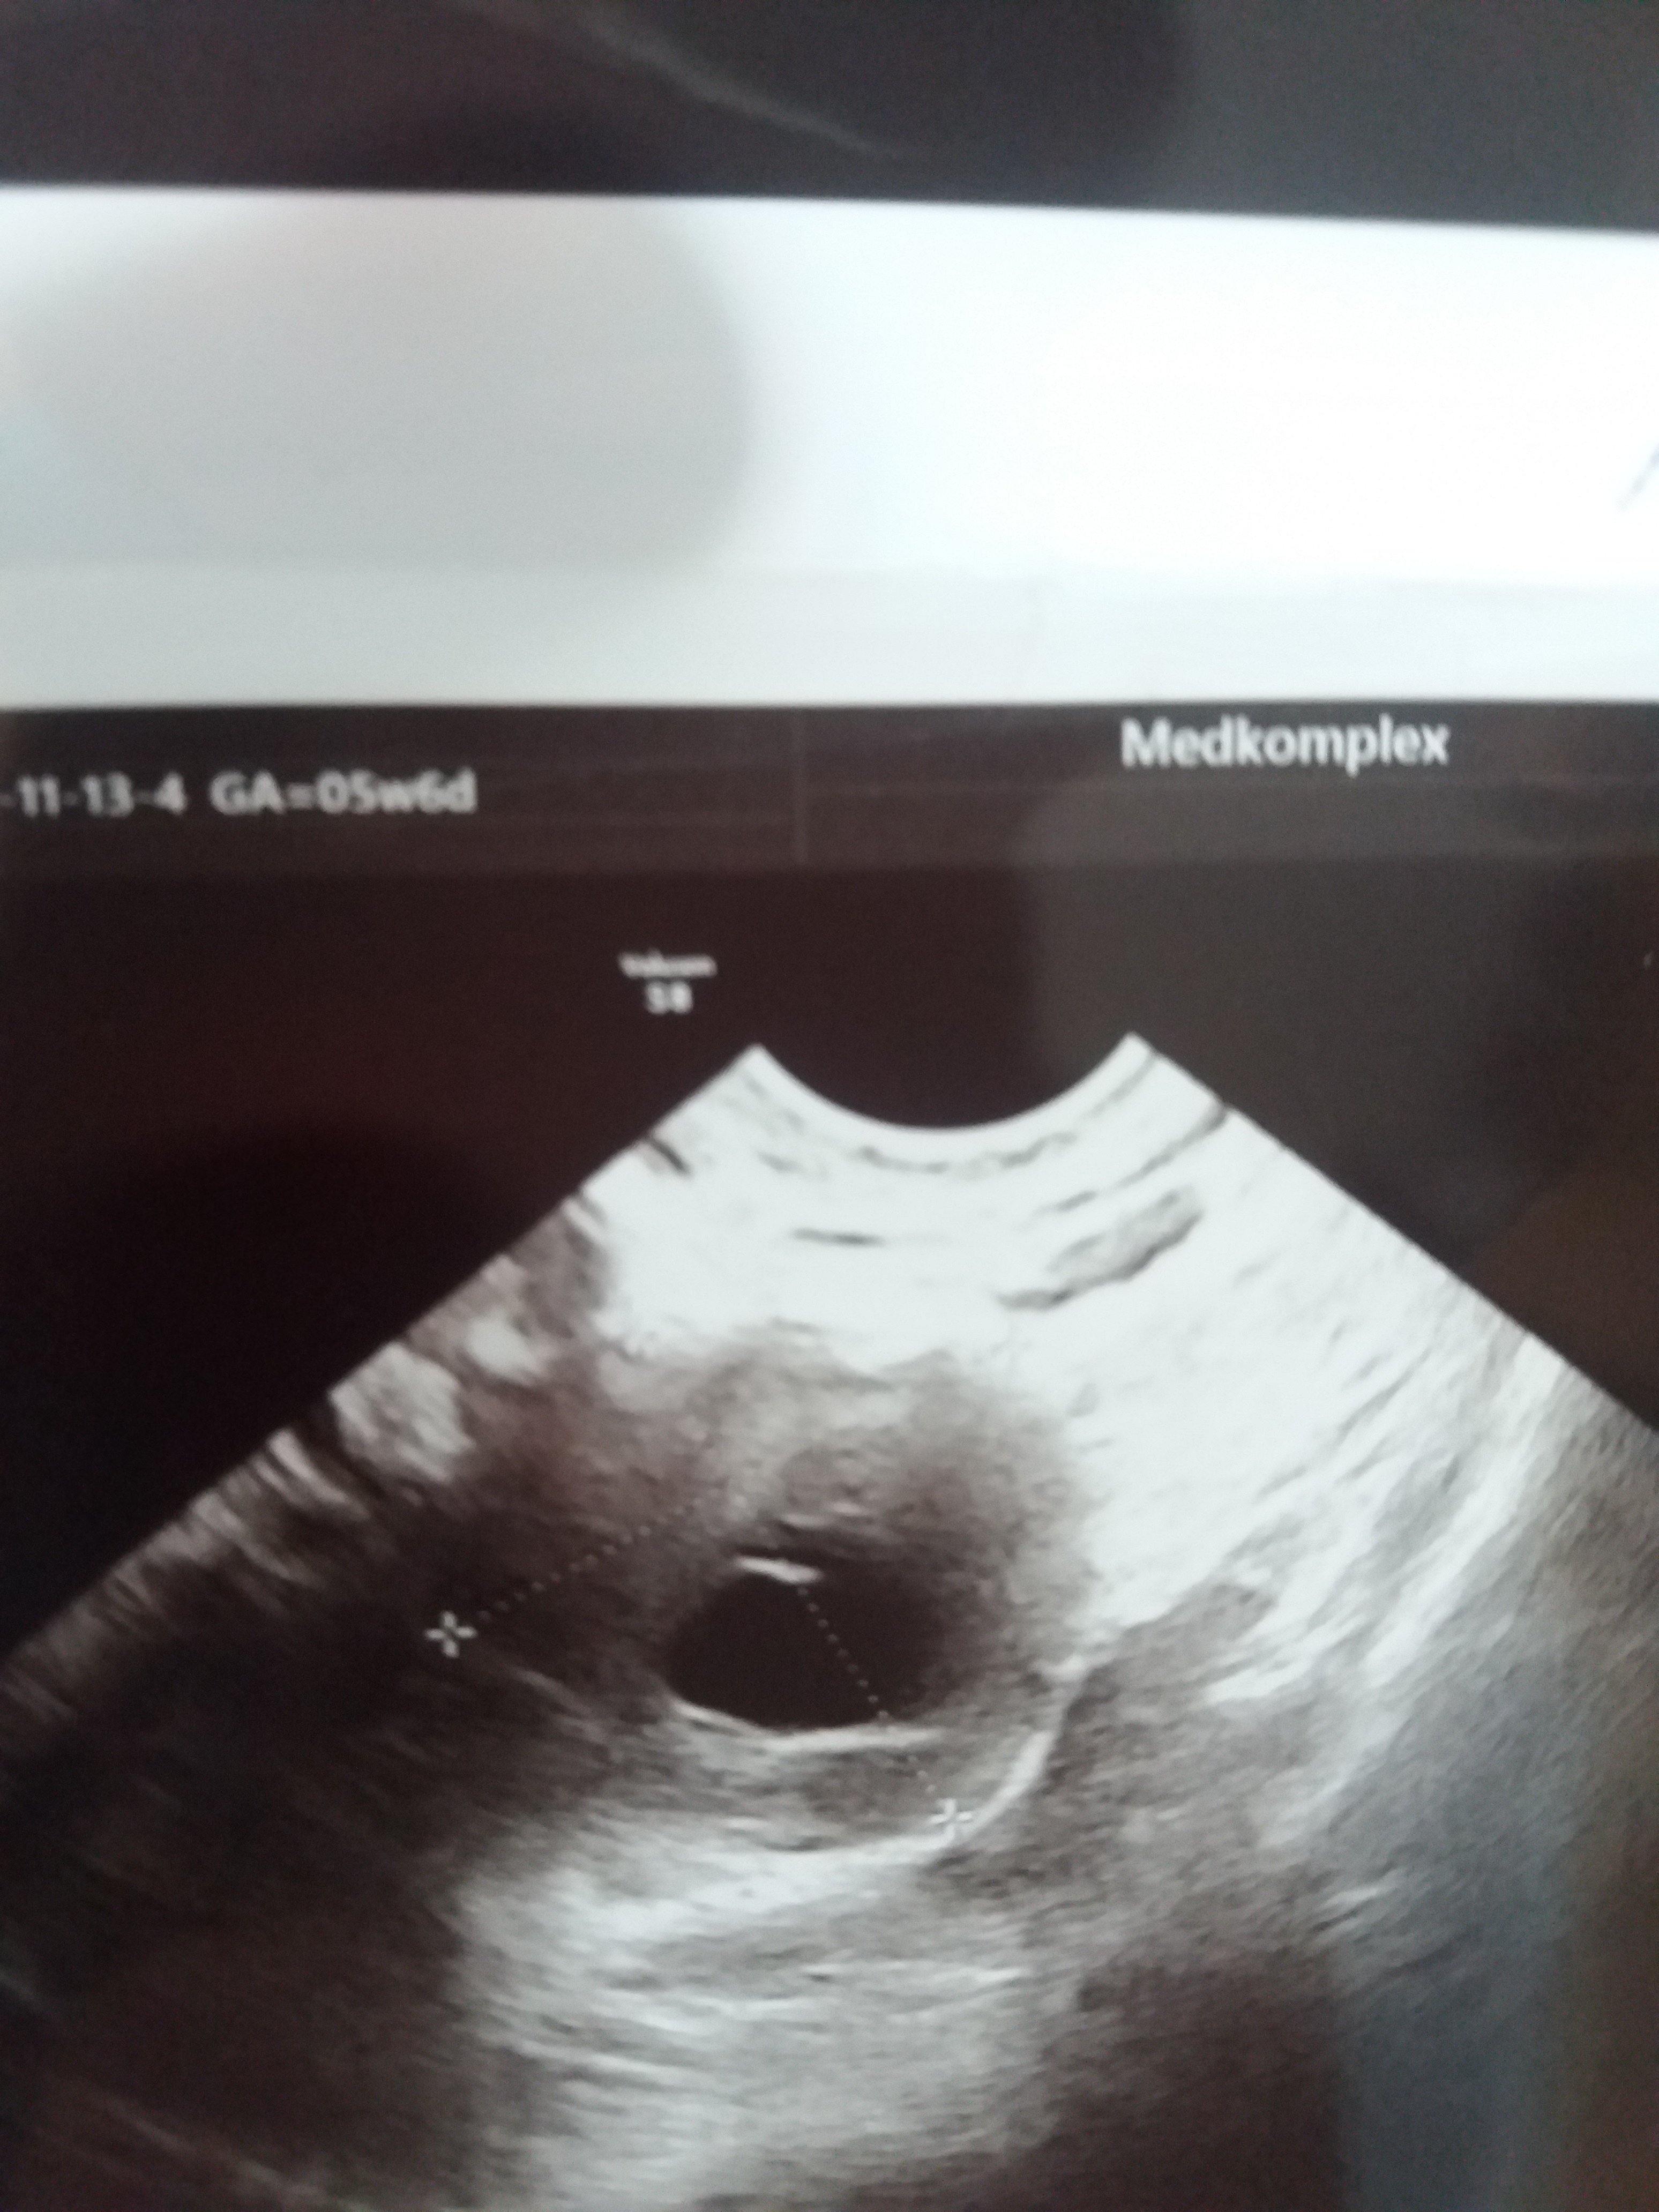

Hej dziewczyny wracam właśnie z wizyty u lekarza i jestem lekko załamana. Zrobił mi usg i mówi ze jestem w środku lekko spuchnięta i zaczerwieniona. Na usg wyszło jakieś coś i lekarka nie wie na ten czas czy to torbiel czy wrzesna ciąża i pęcherzyk. Mam lekkie bóle podbrzusza i parcie na przecherz i z tych nerwów słabo mi się robi. Mam pocZekac tydzień iść

Na betę i wrócić z wynikami. Ale dziwne bo byłam u niej miesiąc temu i na usg było czysto a tu nagle coś 33mm. Miała któraś z was tak bo ja wariuje

@Sylwia199630 O tym pisałam Ci wcześniej - że może być za wcześnie na pęcherzyk. To na USG wygląda jak jakaś torbiel. To jest zdecydowanie za duże na pęcherzyk ciążowy na tym etapie. Ale to jeszcze nic nie oznacza - postaraj się nie stresować i poczekać na wizytę. Powtórz betę, ale tak by mieć drugi wynik z pobrania po 48h.

Na betę i wrócić z wynikami. Ale dziwne bo byłam u niej miesiąc temu i na usg było czysto a tu nagle coś 33mm. Miała któraś z was tak bo ja wariuje Zobacz załącznik 1134710

Ja bym poszła na bete już dziś, nie wiem.co to jest zaznaczone ,ale to nie ciąza, ciąża to byłby tako malutki czarny punkcik